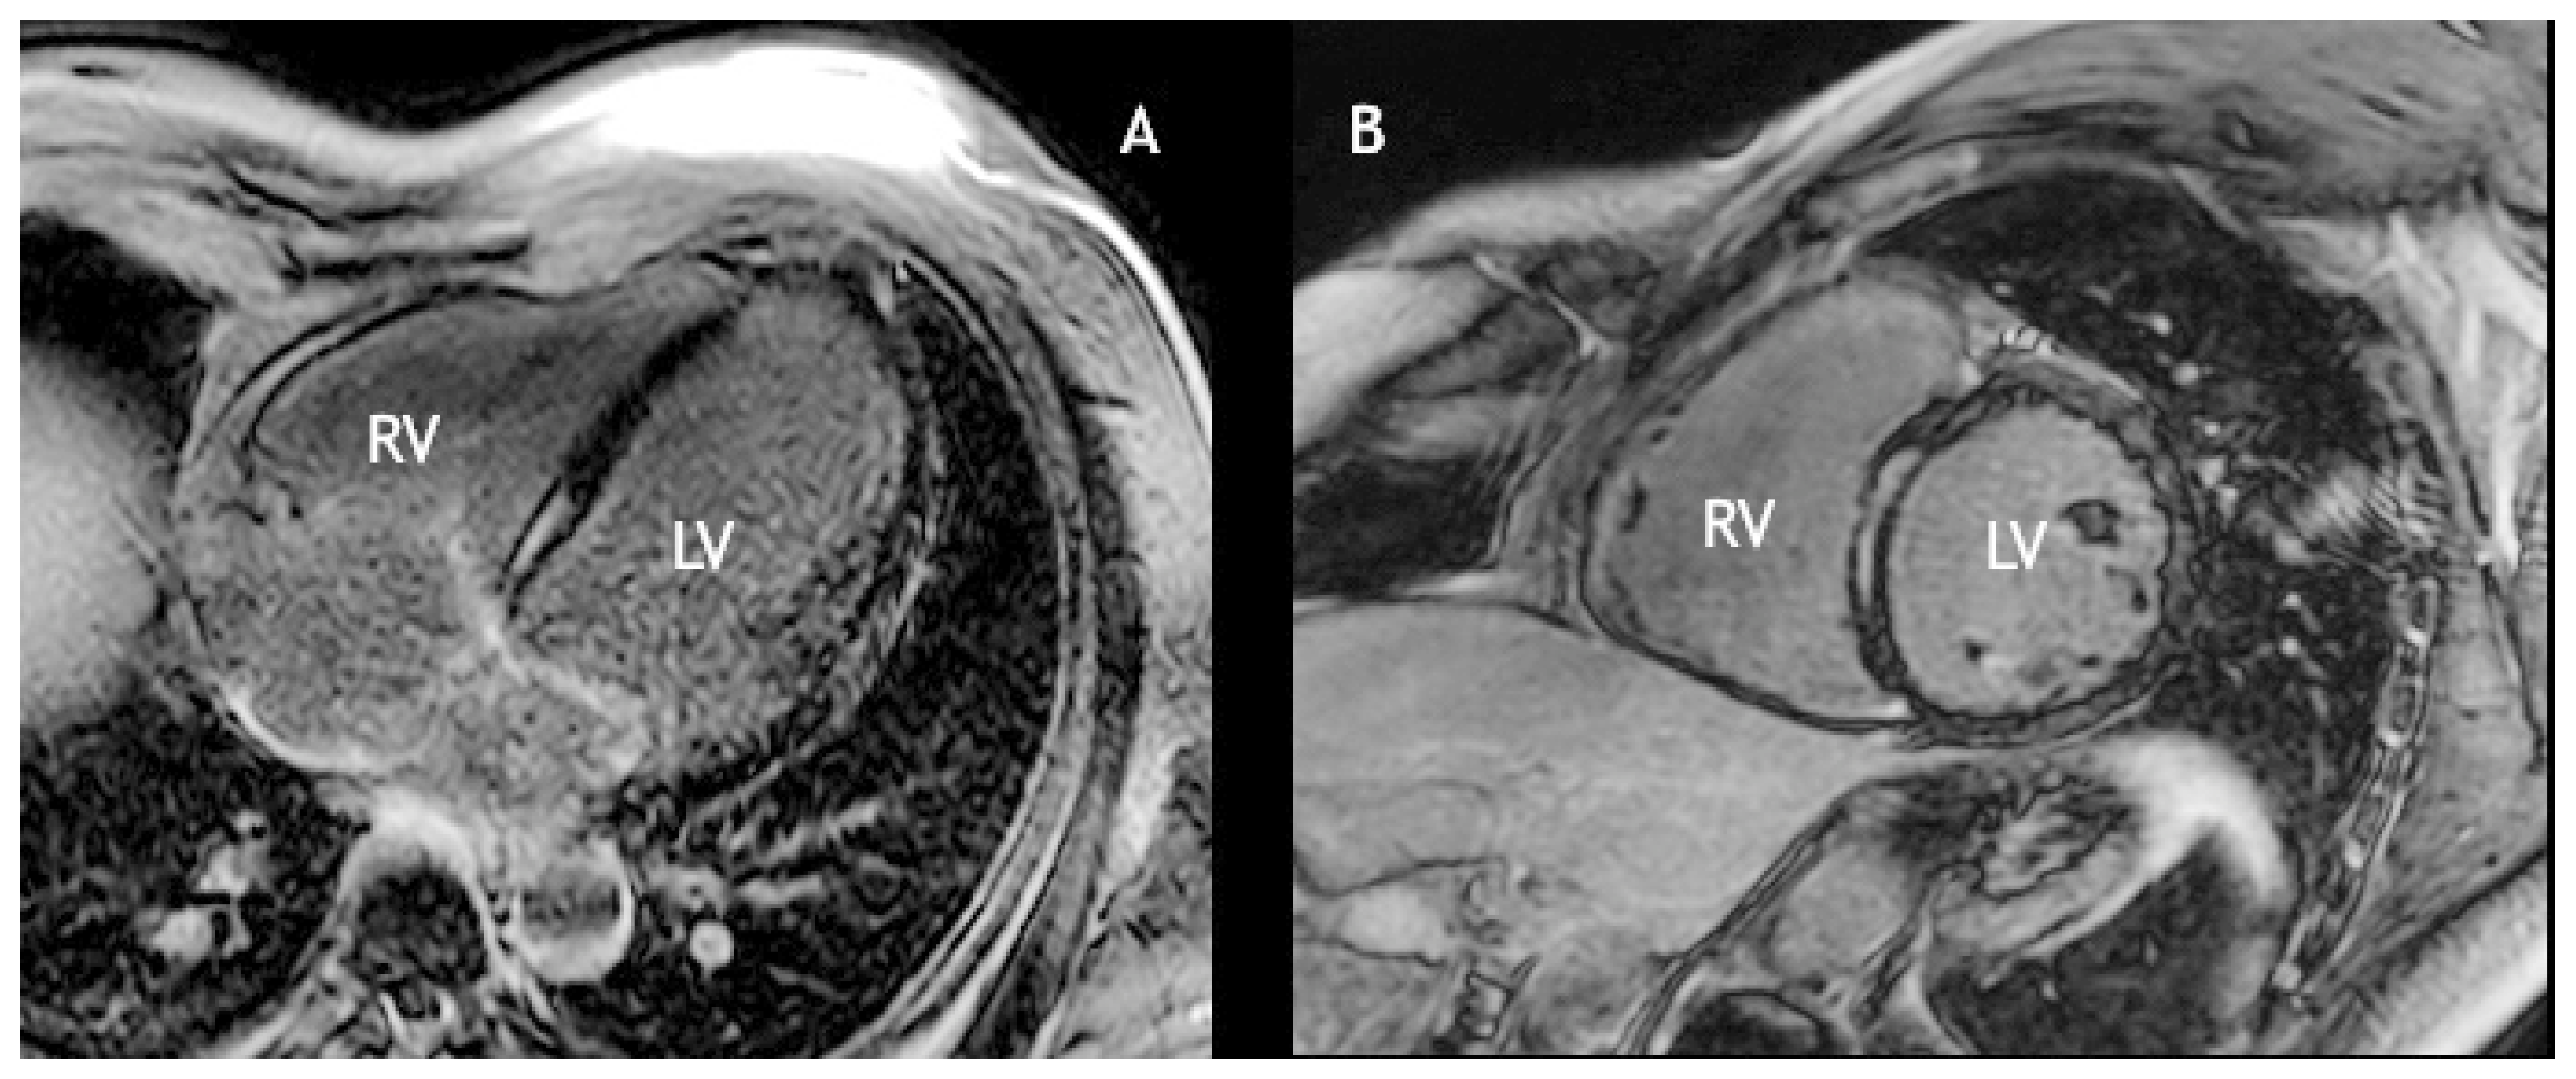

On physical examination he appeared in excellent condition, with weight 90 kg for a height of 185 cm. The pulse was regular and bradycardic at 39 bpm, blood pressure was 130/80 mm Hg. Cardiac and chest auscultation were unremarkable. Chest x-ray showed a slightly dilated cardiac silhouette. The ECG revealed sinus rhythm with 2:1 atrioventricular block (AVB) (Figure 1) alternating with complete AVB (Figure 2). During Holter monitoring there was normal sinus rhythm with persistent high-degree AVB (Mobitz type 2; advanced second degree – 2:1 and 3:1 – and complete AVB) with mean ventricular rate 41 bpm and maximum R-R interval of 4 s. An echocardiogram revealed mild left ventricular dilatation (left ventricular end-diastolic diameter 62 mm), and a subnormal left ventricular ejection fraction (LVEF) of 50% due to septal hypokinesia. Cardiac magnetic resonance imaging (CMR) confirmed the mild left ventricular dilatation and showed linear mid-myocardial late gadolinium enhancement of the basal septum, indicating myocardial fibrosis (Figure 3). On the basis of the family history of DCM, the complete AVB, the mild left ventricular dilatation with sub-normal LVEF and linear mid-myocardial septal fibrosis, we suspected cardiomyopathy due to a lamin A/C (LMNA) gene mutation.

In addition to history, ECG and echocardiography, CMR plays an important role in determining cardiac involvement in LMNA cardiomyopathy. Holmström et al. [16] showed that 88% of patients with LMNA cardiomyopathy had left ventricular myocardial fibrosis. The pattern of enhancement was typically linear and less than 50% of the area of the segment. In all the patients, late gadolinium enhancement occurred in the basal or mid-ventricular septum, which strongly correlated with segmental wall motion abnormalities. Our patient had exactly this typical pattern.

Figure 3. Post-contrast inversion recovery gradient echo images (late gadolinium enhancement) in a four-chamber (A) and short axis view (B), showing linear, mid-myocardial enhancement of the basal ventricular septum, consistent with fibrosis.